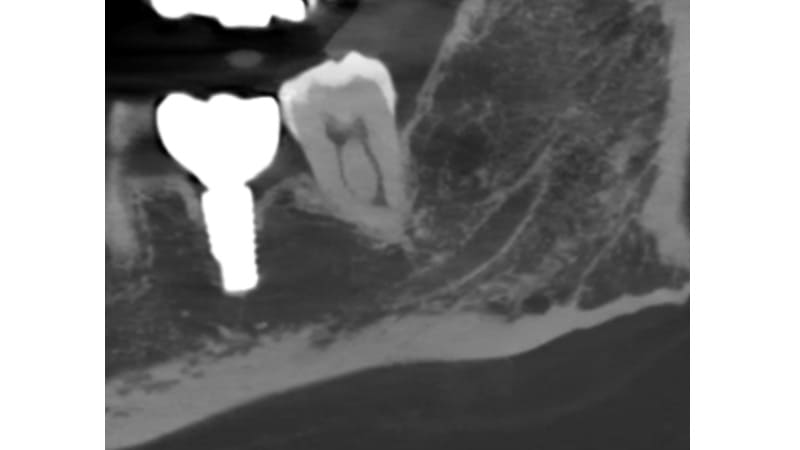

症例④:奥歯が違和感がある

| 治療科目 | 歯周組織再生療法 |

|---|---|

| 主訴 | 奥歯が違和感がある |

| 治療期間 | 1年 |

| 治療費 | 220,000円 |

| 治療内容 | 抜髄後、エムドゲインとバイオスを使い再生療法を行った。 |

| 治療のリスク | 角化歯肉の状態により再度感染を起こす可能性があり、遊離歯肉移植の併用が必要なこともあります。清掃方法によって再感染する可能性があり、定期的な通院でチェックしていく必要があります。 |